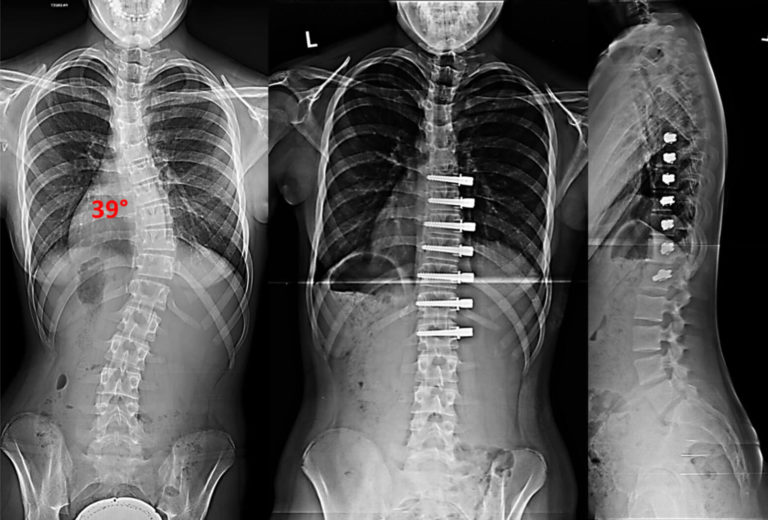

Before and after pics from my surgery (6/26/19) r/scoliosis Rods For Scoliosis Surgery modern surgical approaches and instrumentation—rods, screws, hooks, and/or wires placed in the spine—have enabled spinal fusion surgeries to achieve better curvature correction and faster recovery times than in the past. learn about spinal fusion, the most common surgery for scoliosis, which involves metal rods and bone grafts to realign and fuse the curved vertebrae. scoliosis rod surgery,. Rods For Scoliosis Surgery.

Scoliosis X Ray Before And After Rods For Scoliosis Surgery scoliosis surgery, also known as spinal fusion surgery, is performed to correct curvature of the spine of more than 25 to 30 degrees. in adolescent idiopathic scoliosis, the primary surgery used today is fusion surgery. if the scoliosis is progressing rapidly at a young age, surgeons can attach one or two expandable rods along the spine that. Rods For Scoliosis Surgery.